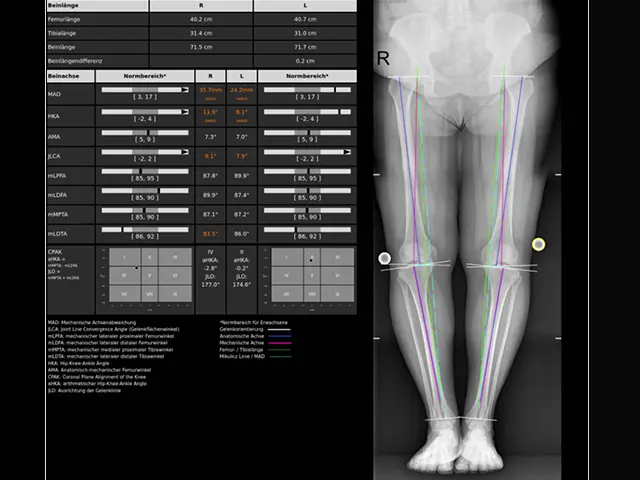

3. AI-supported axis measurement: For precise planning, we use LAMA® AI software, which calculates all relevant parameters of your joint geometry precisely from a full-leg X-ray. This allows us to identify any misalignment in detail.